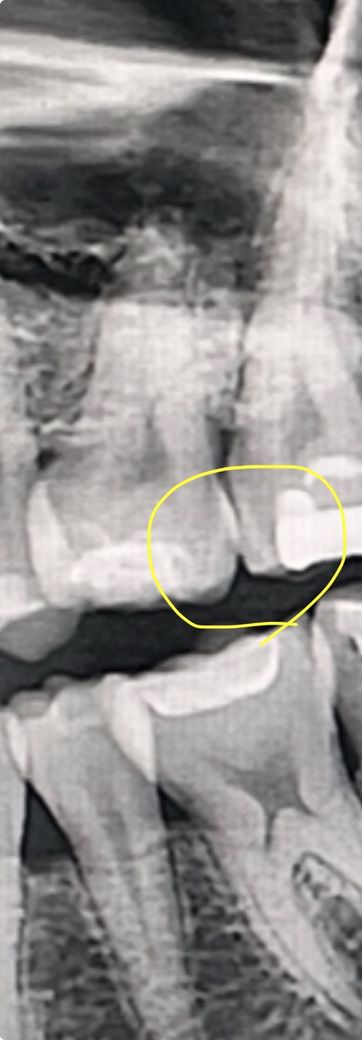

엑스레이 찍은건데 충치같기도 하고 아닌거 같기도 하고… 치과선생님은 별말없으셔셔요 ㅠ

엑스레이 상으로 검은 부분은 거의 충치라단데…겉으로보기에는 아무 이상없는데 인접면 충치인가해서요 ㅠ

엑스레이 상으로 치아 사이에 인접면 충치가 약간 잇는거 같습니다. 일단은 관리를 잘하시는게 중요할것같습니다.

…겉으로보기에는 아무 이상없는데 인접면 충치인가해서요?-> 충치같지만 매우 초기라 관리만해도 됩니다.

사진으로 봤을 때 음영이 보이긴 합니다. 하지만 육안으로 큰 문제가 없다면 큰 문제가 없을 가능성이 높습니다.

얕은 충치의 가능성도 있어보입니다

다만, 엑스레이상 검은 부분이 전부다 충치는 아닙니다 엑스레이는 왜곡, 중첩을 비롯하여 defect가 많습니다